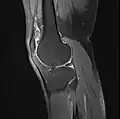

MRI

Both anterior cruciate ligament (ACL) and posterior cruciate ligaments (PCL) are hypointense on both T1 and T2 weighted images of MRI. However, some high signal striations are often seen at the distal part of the ACL, making ACL higher intensity than PCL on MRI scans.[20]